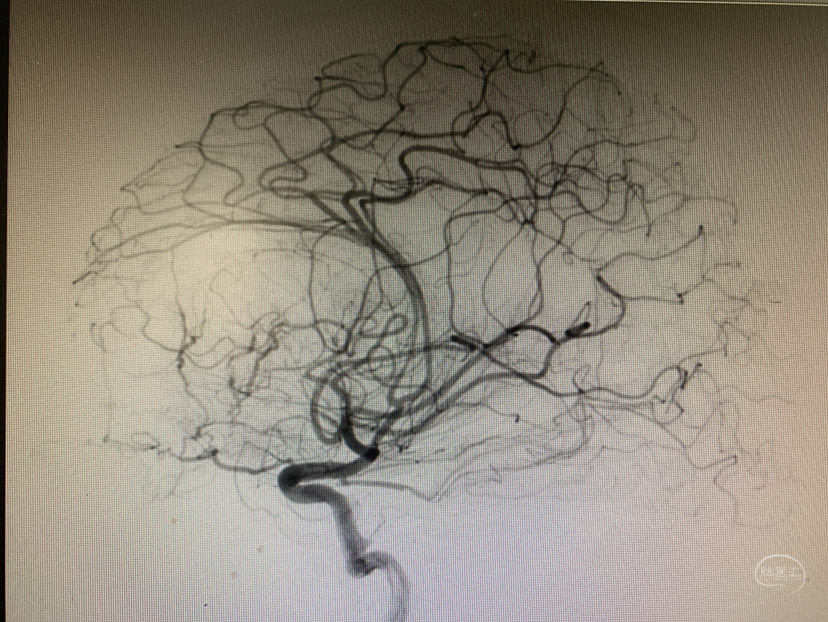

术前造影

神志昏迷双瞳散大对光反射迟钝入院,入院后甘露醇脱水加地米静滴后患者神经功能有改善,能摸索定位,瞳孔反射改善。考虑占位大直接切除可能出血多,拟术前栓塞处理,但造影发现栓塞不易风险高后放弃栓塞。